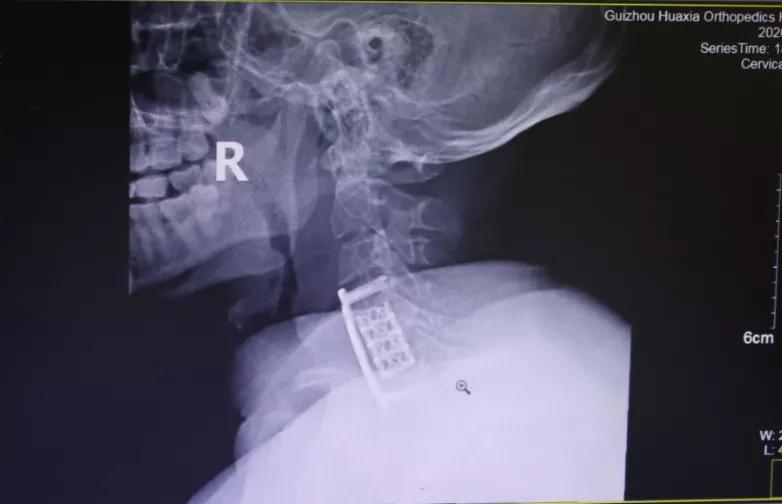

做了全面的检查后,胡阿姨被诊断为:颈椎病(脊髓型);颈椎间盘突出症 ;颈椎后纵带骨化症;肝功能不全 。患者诊断明确,存在明显手术指征,需行手术治疗,进行椎管减压,神经根松解,以阻止病变进一步发展,防止出现更加严重的双下肢瘫痪或大、小便功能障碍。

面对患者严重的病情,为使患者得到最佳、最快的治疗,12月18日,完善术前检查后,为胡阿姨实施了手术治疗。术后,疼痛、麻木等症状大大减轻。